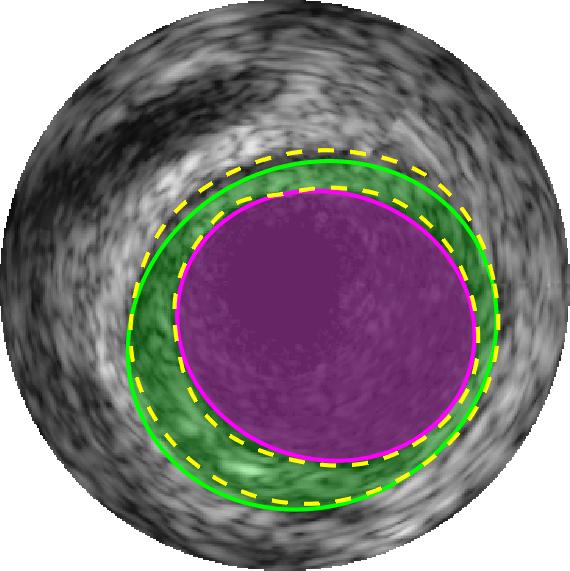

Qualitative evaluations are illustrated in Figure 4 and show the successful segmentation results of the proposed EREL selection strategy for 20 IVUS frames. The lumen areas are highlighted by the magenta colour while the media regions are green. Also, the manually annotated contours for both lumen and media are drawn as yellow dashed lines. As we can see, the chosen frames contain a variety of lumen and media morphologies.